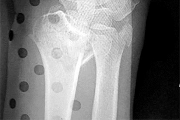

A 65-year-old active female presents to the emergency department after a mechanical fall. She complains of severe right groin pain and inability to bear weight. A representative radiograph of her injury is shown below. Assuming the image demonstrates a displaced (Garden IV) femoral neck fracture, which of the following is the most appropriate surgical intervention to maximize her functional outcome and minimize her lifetime revision rate?

Options:

Correct Answer: Total hip arthroplasty

Explanation:

For active, physiologically young older adults (typically 65-75 years old) with displaced femoral neck fractures, Total Hip Arthroplasty (THA) is the treatment of choice. Multiple randomized controlled trials have demonstrated that THA yields better long-term functional outcomes (e.g., higher Harris Hip Scores) and lower reoperation rates compared to hemiarthroplasty. Hemiarthroplasty (unipolar or bipolar) is generally reserved for lower-demand, older, or cognitively impaired patients. Internal fixation with cannulated screws for a Garden IV fracture in this age group carries an unacceptably high risk of nonunion and avascular necrosis.